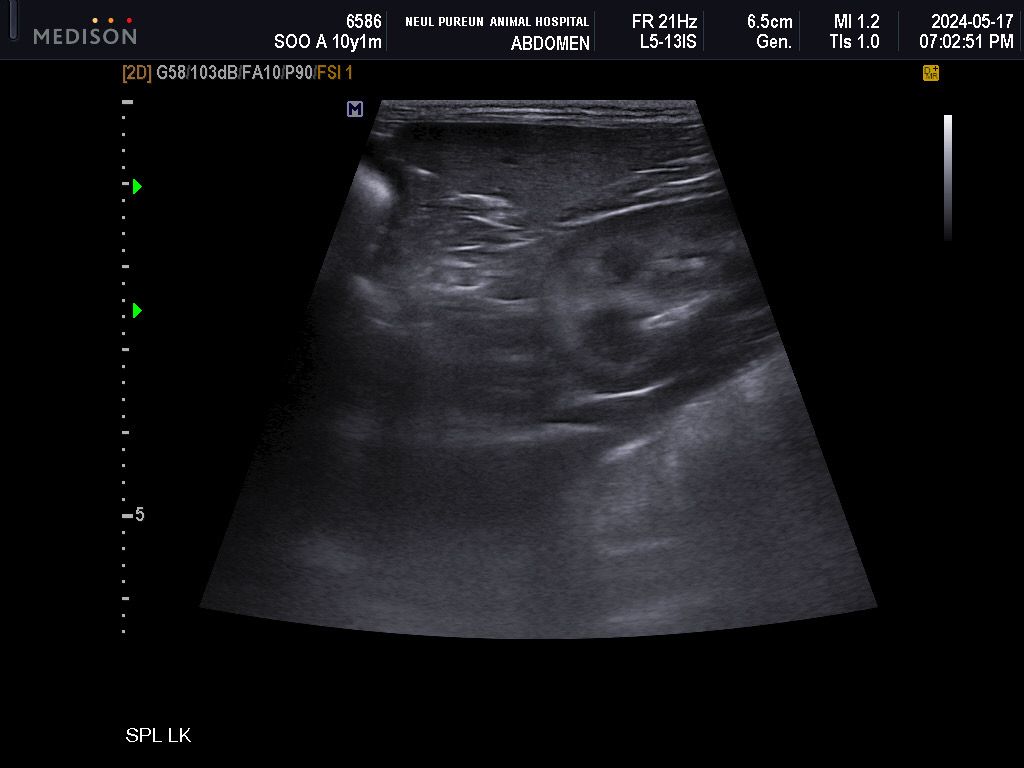

저희 강아지 5월에 찍었던 초음파인데 이게 비장 맞나요? 이번에 찍은 초음파에선 비장에 작은 결절이 하나 보였는데 이때도 보였던 건지 알 수 있을까요? 그 외 특이사항이 있는지도 알고 싶어요

이 부분이 비장 조직 사진이고 해당 사진에서는 결절성 병변이 보이지 않습니다. 다만 해당 사진은 비장의 긴 여역의 단면에 해당하고 전체 비장의 영상자료는 아니기에 이번에 발견된 결절이 그때는 없었다고 말할 수는 없습니다.